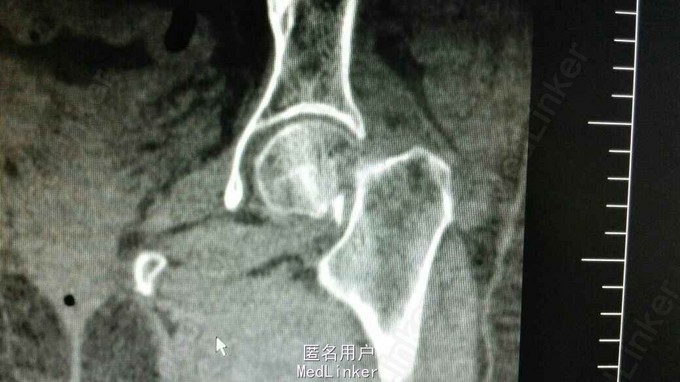

左下肢外旋30度、短锁2cm 畸形,左髋部压痛、左下肢轴向叩击痛(+),左髋部主动活动受限 髋关节正侧位片及骨盆CT提示左股骨颈头下型骨折

诊断:左股骨颈骨折(头下型,Garden IV期) 治疗:闭合牵引复位开心钉内固定术